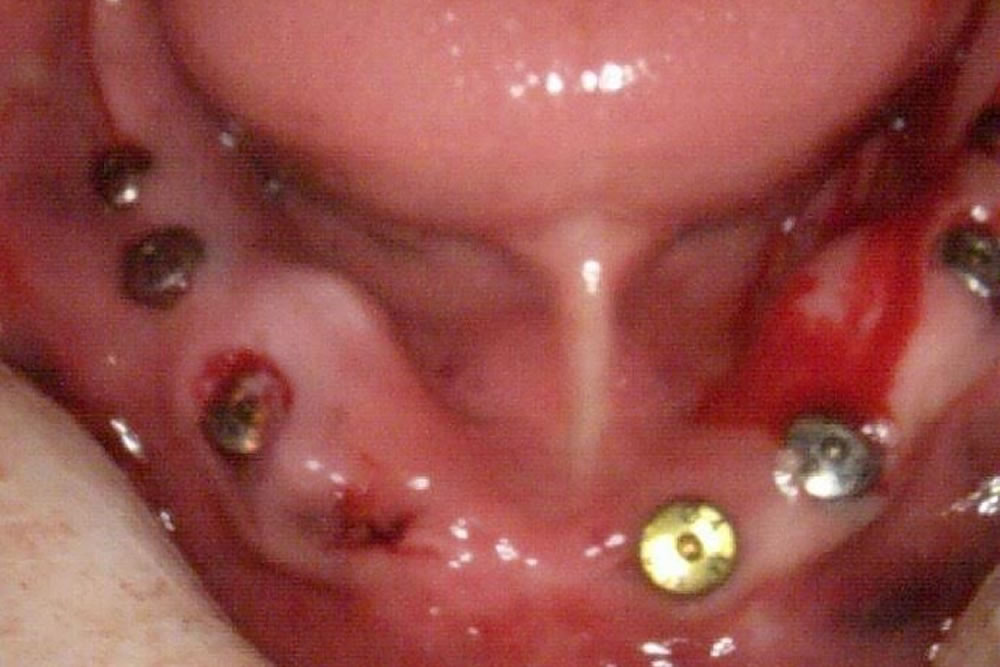

抜歯・インプラント埋入手術の実施

歯を抜いて即日インプラント埋入、骨造成を行い、治療用入れ歯を斬感的にセットしました。

インプラントの本数としては、強度的にも心配という事で8本を希望されました。